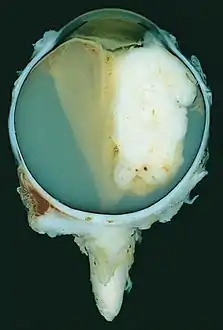

| A pathology specimen of a retinoblastoma tumor from an enucleated eye of a 3-year-old female | |

Large exophytic white tumor with foci of calcification producing total exudative retinal detachment